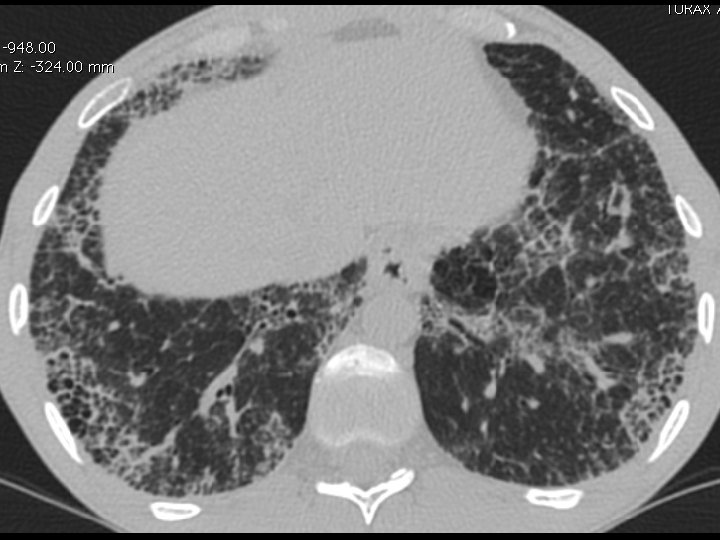

High-resolution CT scan

Subpleural, basal predominance Reticular abnormality Honeycombing with traction bronchiectasis UIPUIP Pattern

Subpleural, basal predominance Reticular abnormality Honeycombing with traction bronchiectasis Profuse micronodules UIPUIP Pattern Inconsistent with UIP Pattern

39 yo caucasian male, works in car collision repair and painting Multiple allergies, Gastroesophageal reflux disease and Thrombocytopenia of unknown etiology Smoker. No drugs CT: Reticular abnormality and honeycombing of subpleural basal predominance + micronodules Lung function tests: decreased diffusion capacity of the lung Blood tests: small increase of ESR and CRP; Autoimmune screening blood tests were normal BAL: normal celularity, with a mild increase in the neutrophil and eosinophil count

39 yo caucasian male, works in car collision repair and painting Multiple allergies, Gastroesophageal reflux disease and Thrombocytopenia of unknown etiology Smoker. No drugs CT: Reticular abnormality and honeycombing of subpleural basal predominance + micronodules Lung function tests: decreased diffusion capacity of the lung Blood tests: small increase of ESR and CRP; Autoimmune Screening Blood Tests were normal BAL: normal celularity, with a mild increase in the neutrophil and eosinophil count Definitive diagnosis can be established? Additional diagnostic tests required? Which tests?